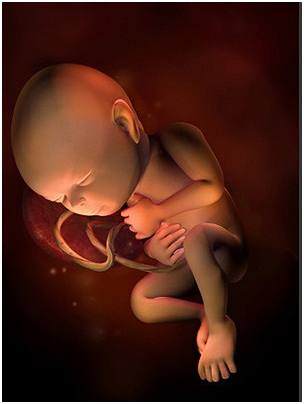

怀孕第8周如果还没检查过的准妈妈,这周一定要开始第一次产前检查啦!胎儿的胚胎器官已经开始具...

怀孕第8周如果还没检查过的准妈妈,这周一定要开始第一次产前检查啦!胎儿的胚胎器官已经开始具... -

怀孕第10周在怀孕前,你的子宫大概和小香梨一样大,但现在已经长到一个大橙子那么大了。这段时间...

怀孕第10周在怀孕前,你的子宫大概和小香梨一样大,但现在已经长到一个大橙子那么大了。这段时间... -

怀孕第11周11周开始,你的早孕反应开始慢慢减轻,现在你也不必为流产过多担心了。为了生个健康...

怀孕第11周11周开始,你的早孕反应开始慢慢减轻,现在你也不必为流产过多担心了。为了生个健康... -

怀孕第14周祝贺你,你的肚肚就要显露出来了!宝宝身体的所有基本构造也已经形成,尽管它们很小,...

怀孕第14周祝贺你,你的肚肚就要显露出来了!宝宝身体的所有基本构造也已经形成,尽管它们很小,... -

怀孕第15周现在你需要做一次产前诊断了,15~18周之间是做产前诊断的最佳时期;怀孕改变了你...

怀孕第15周现在你需要做一次产前诊断了,15~18周之间是做产前诊断的最佳时期;怀孕改变了你... -

怀孕第12周现在胎儿身体的雏形已经发育完成了,你的脸和脖子上可能会不同程度地出现黄褐斑,腹部...

怀孕第12周现在胎儿身体的雏形已经发育完成了,你的脸和脖子上可能会不同程度地出现黄褐斑,腹部... -

怀孕第13周胎儿脸部更加清晰了,肚子开始变大,妊娠趋于稳定,妊娠反应消失,食欲也很不错。这时...

怀孕第13周胎儿脸部更加清晰了,肚子开始变大,妊娠趋于稳定,妊娠反应消失,食欲也很不错。这时... -